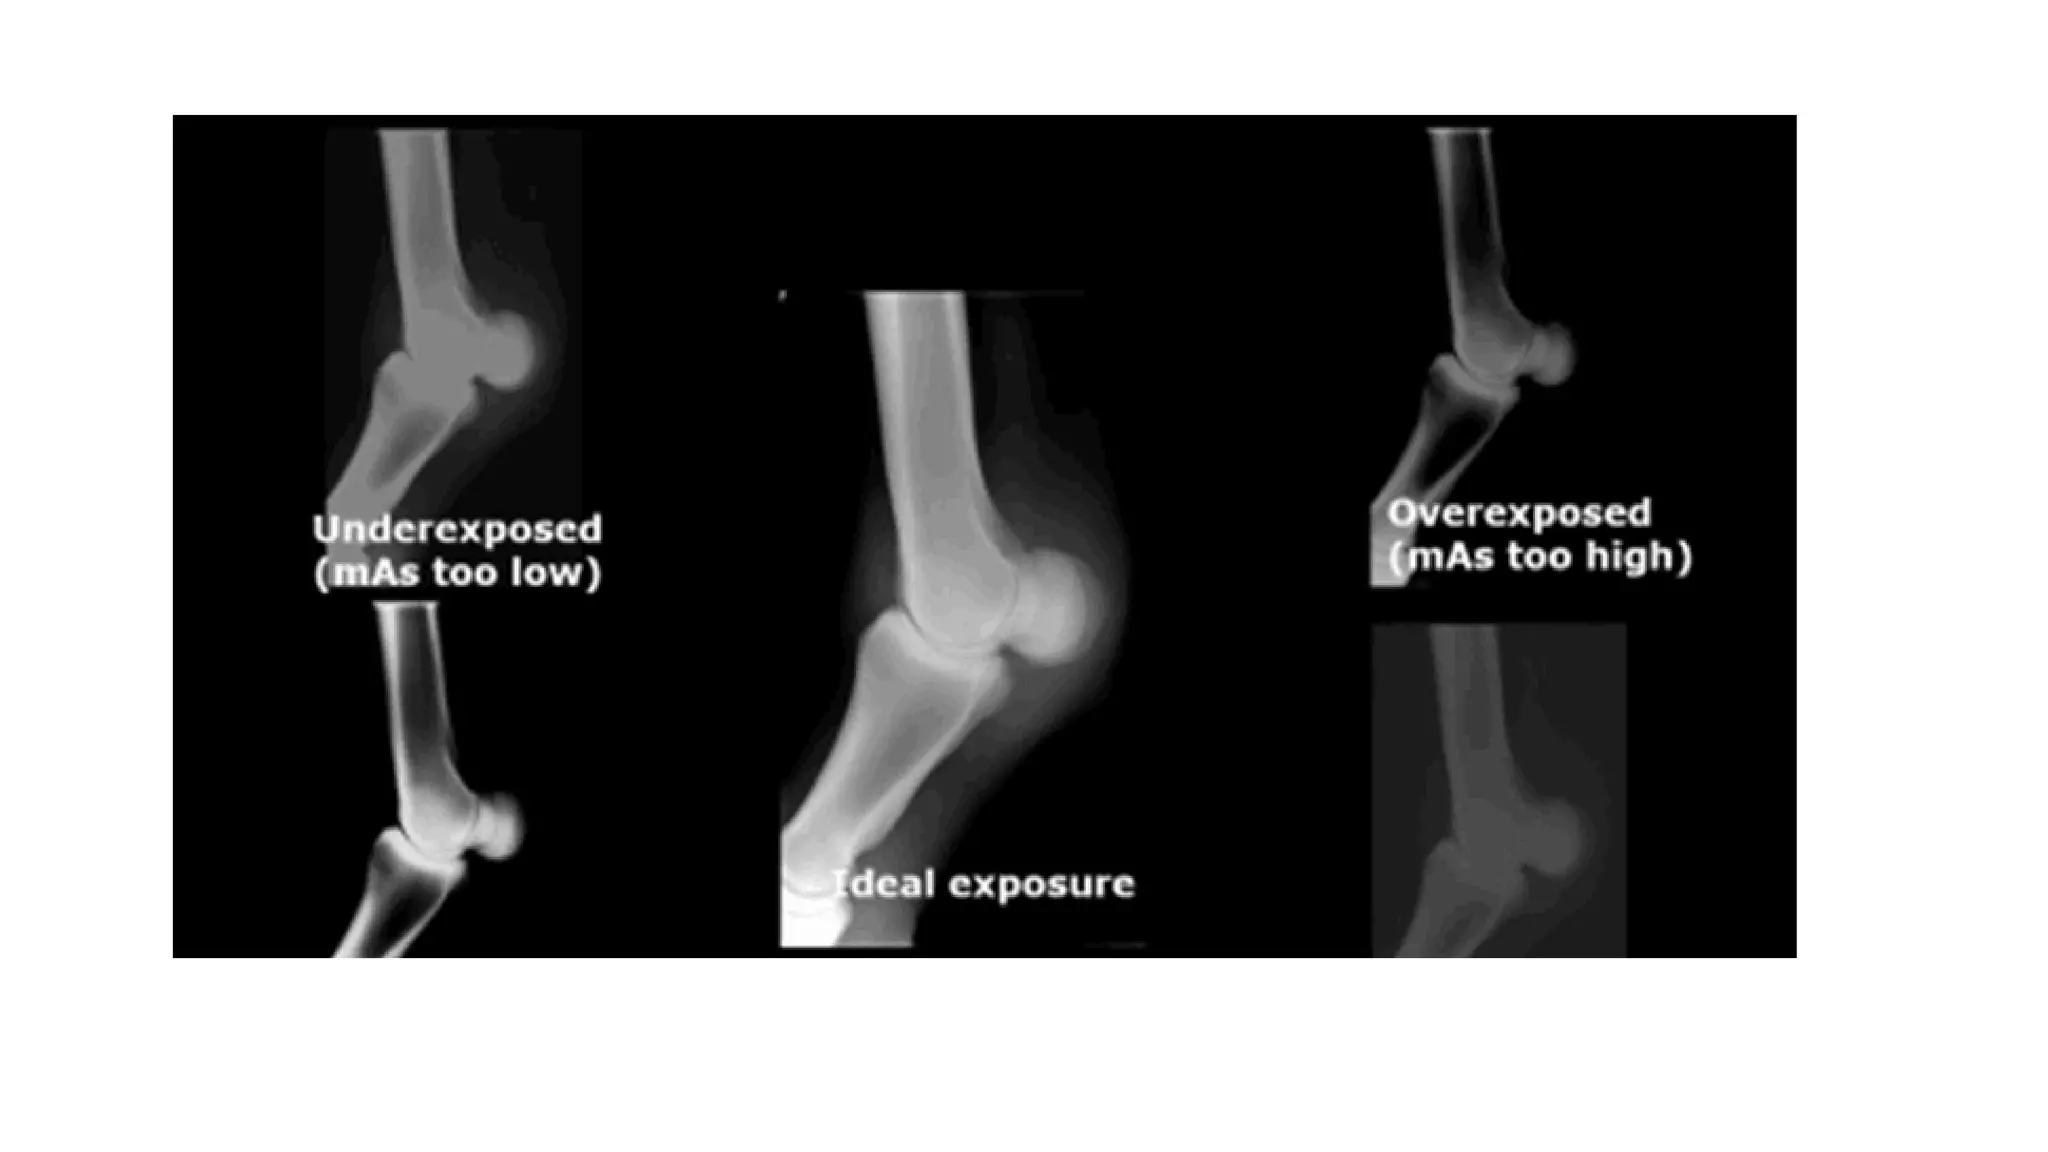

The terms "technique" and "kVp, mA, and mAs" relate

to the exposure factors. Technique is like the light

of a film camera.

If a photo is shot in low light, the image is

underexposed since there isn't enough light to

expose the film.

TECHNIQUE

The photograph is overexposed when exposed to

strong light.

This also applies to film radiography. The film is underexposed

when exposure procedures are used at too low a level.

Overexposure will occur on the film if they are too high